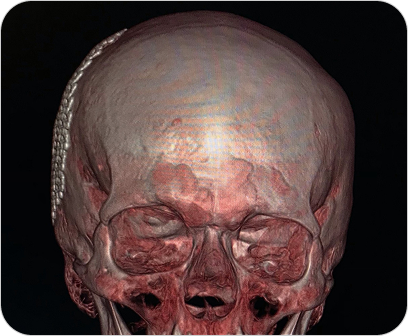

Reconstrucción 3D en Tomografía

Es una técnica avanzada que permite convertir las imágenes obtenidas por tomografía computada en modelos tridimensionales. Estas reconstrucciones permiten visualizar estructuras anatómicas de forma realista, facilitando diagnósticos más precisos y una mejor planificación quirúrgica o terapéutica.

Las reconstrucciones tridimensionales a partir de tomografía computada permiten visualizar la anatomía de forma realista y precisa, facilitando diagnósticos y cirugías complejas.

¿PARA QUE SE UTILIZA?

- Evaluación detallada de fracturas complejas, articulaciones y columna vertebral.

- Estudio anatómico previo a cirugías (traumatológicas, maxilofaciales, cardiovasculares).

- Visualización de vasos sanguíneos, tumores o malformaciones desde distintos ángulos.

- Planificación prequirúrgica más segura y personalizada.

- Educación médica y explicación visual a pacientes.

¿POR QUÉ ES UN ESTUDIO DESTACADO?

- Imágenes más claras y comprensibles para médicos y pacientes.

Facilita una mayor precisión diagnóstica. - Permite una visión global y tridimensional de la anatomía.

- Complemento ideal para especialidades como traumatología, neurocirugía, cirugía maxilofacial y oncología.

Reconstrucción 3D en Tomografía

Es una técnica avanzada que permite convertir las imágenes obtenidas por tomografía computada en modelos tridimensionales. Estas reconstrucciones permiten visualizar estructuras anatómicas de forma realista, facilitando diagnósticos más precisos y una mejor planificación quirúrgica o terapéutica.

Las reconstrucciones tridimensionales a partir de tomografía computada permiten visualizar la anatomía de forma realista y precisa, facilitando diagnósticos y cirugías complejas.

¿PARA QUE SE UTILIZA?

- Evaluación detallada de fracturas complejas, articulaciones y columna vertebral.

- Estudio anatómico previo a cirugías (traumatológicas, maxilofaciales, cardiovasculares).

- Visualización de vasos sanguíneos, tumores o malformaciones desde distintos ángulos.

- Planificación prequirúrgica más segura y personalizada.

- Educación médica y explicación visual a pacientes.

¿POR QUÉ ES UN ESTUDIO DESTACADO?

- Imágenes más claras y comprensibles para médicos y pacientes.

Facilita una mayor precisión diagnóstica. - Permite una visión global y tridimensional de la anatomía.

- Complemento ideal para especialidades como traumatología, neurocirugía, cirugía maxilofacial y oncología.